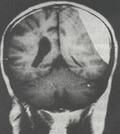

2.MRI(磁共振成像)

硬膜外血腫在亞急性期與慢性期T、T加權圖像均為高信號。